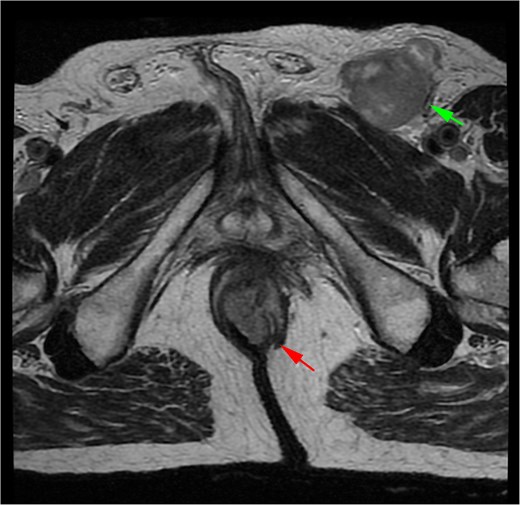

A 71-year-old man reported pain and bleeding associated with an anal tumor over 6 months. Colonoscopy showed no colorectal lesions, but an anal tumor was identified in the anterior region. It was fixed, firm, and approximately 4 cm in diameter, pink, with signs of superficial erosion and recent bleeding (Fig. 5). A biopsy confirmed the presence of ulcerated malignant melanoma with deep invasion greater than 4 mm and mild pigmentation. IHC was positive for Melan A, S100, and CD117 (Fig. 6). Blood tests were within normal limits. MRI revealed a lesion in the lower two-thirds of the anal canal (35 × 24 × 35 mm), located between the 12 and 1 o’clock positions, infiltrating the external sphincter and perianal fat (Fig. 7). Additionally, multiple metastatic lymphadenopathies were identified in the left (44 × 34 mm) and right (10 × 10 mm) inguinal regions, as well as in the internal and external iliac chains, which were histologically confirmed. The CT scan supported these findings, indicating the presence of retroperitoneal metastatic lymphadenopathies. The multidisciplinary committee recommended immunotherapy with nivolumab (240 mg IV every 14 days). After 12 treatment cycles, the patient showed good tolerance and adherence, with no evidence of disease progression.

MRI of Case 2 shows an infiltrating anal tumor involving the internal and external sphincters, as well as perianal adipose tissue (lower arrow), with associated inguinal lymphadenopathy (upper arrow). The tumor demonstrates high signal intensity on axial T2-weighted imaging.